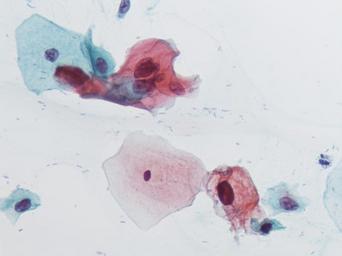

Keywords: lesión intraepitelial escamosa de bajo grado lesiónintraepitelialescamosadebajogrado citología de cuello uterino citologíadecuellouterino citología exfoliativa ginecológica citologíaexfoliativaginecológica citología de cribado citologíadecribado citología anatomía patológica anatomíapatológica bethesda 2001 bethesda2001 osuna cérvix uterino cérvixuterino hpv españa screening lsil enfermedades de transmisión sexual enfermedadesdetransmisiónsexual imágenes de citología ginecológica imágenesdecitologíaginecológica papanicolaou test de papanicolaou testdepapanicolaou tinción de papanicolaou tincióndepapanicolaou drawing white background Células con núcleo y citoplasma aumentado de tamaño, núcleos irregulares, como plumosos, tendencia al color naranja de muchas células, halos en algunos casos, núcleos dobles en otros, algunos núcleos hipercromáticos. Células con núcleo y citoplasma aumentado de tamaño, núcleos irregulares, como plumosos, tendencia al color naranja de muchas células, halos en algunos casos, núcleos dobles en otros, algunos núcleos hipercromáticos.